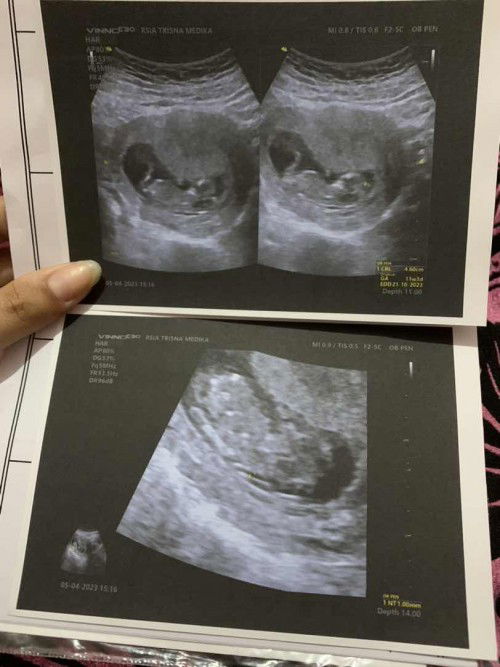

halo bunda" saya mau nanya nih😁 hari ini barusan cek usg ternyata sudah memasuki usia kehamilan 11w3d lalu saya tanya kedokternya tentang kelainan down syndrom , dan setelah itu sm dokternya dicek bund ternyata aman seperti di gambar NT nya 1.00 kalau sudah dicek begitu berarti sudah aman ya bund? ga berubah kan hihi maaf ya bund maklum masih hamil anak pertama bnyak overthingkingnya🙏😁 sebelumnya terimakasih bagi yang sudah membaca dan menanggapi bunda🙏 #ingintahu #firstmom